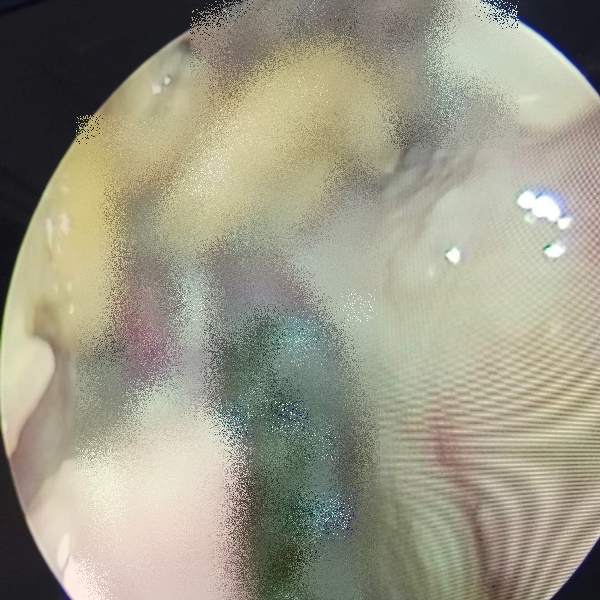

Giòi làm tổ trong hốc mũi bệnh nhân (Ảnh: Bệnh viện cung cấp).

Tại đây, bác sĩ và ekip phẫu thuật tiến hành phẫu thuật nội soi mở các hốc xoang thám sát và gắp hàng chục con giòi sống cùng nhiều tổ chức hoại tử trong hốc mũi người bệnh.